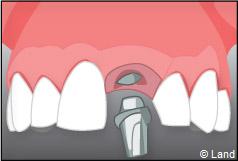

Exemple d’un implant unitaire pour remplacer une dent antérieure manquante.

À l’issue de sa mise en place chirurgicale, une bague de cicatrisation en titane peut être directement vissée sur l’implant. Ainsi une seconde chirurgie ne sera pas nécessaire pour découvrir l’implant.

Pour finir, une prothèse sera mise sur cet implant qui se comportera comme une racine artificielle.